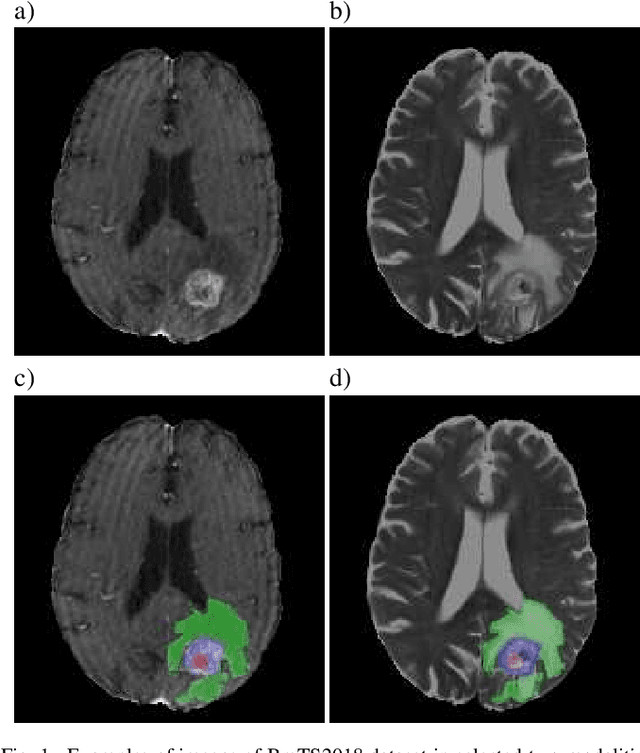

Over the last few years, deep learning has proven to be a great solution to many problems, such as image or text classification. Recently, deep learning-based solutions have outperformed humans on selected benchmark datasets, yielding a promising future for scientific and real-world applications. Training of deep learning models requires vast amounts of high quality data to achieve such supreme performance. In real-world scenarios, obtaining a large, coherent, and properly labeled dataset is a challenging task. This is especially true in medical applications, where high-quality data and annotations are scarce and the number of expert annotators is limited. In this paper, we investigate the impact of corrupted ground-truth masks on the performance of a neural network for a brain tumor segmentation task. Our findings suggest that a) the performance degrades about 8% less than it could be expected from simulations, b) a neural network learns the simulated biases of annotators, c) biases can be partially mitigated by using an inversely-biased dice loss function.